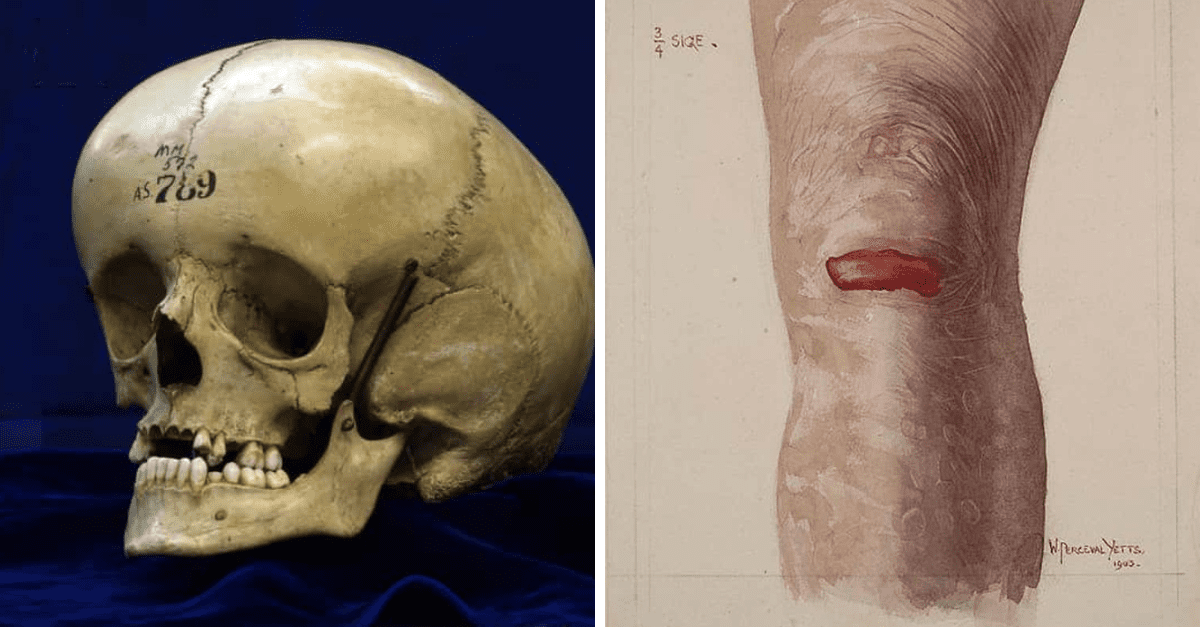

Epidermolysis bullosa postihuje kožu

Epidermolysis bullosa alebo aj choroba motýlích krídiel je stav, ktorý spôsobuje, že koža postihnutého jedinca sa stáva veľmi krehkou a málo odolnou v dôsledku čoho sa na nej často vytvárajú pľuzgiere, koža praská, vznikajú otvorené rany (človek má tendenciu si svrbivú pokožku poškrabať, čím si svoj stav zhoršuje).

Pľuzgiere sa môžu vytvárať aj na slizniciach, čo v prípade, že je postihnutá sliznica hltanu alebo pažeráku môže spôsobiť bolestivé prehĺtanie. Problém tkvie v géne COL7A1, ktorý vytvára proteín potrebný pre vytvorenie molekúl, ktoré tvoria spojivové tkanivá.